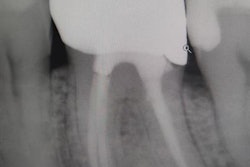

Dr. Bill Kotonias.The thought of having "to do this" for Kotonias and his practice meant adding technology and bringing the fabrication of crowns in-house thanks to in-office milling. This included bringing in the glidewell.io in-office solution and pivoting to Glidewell's BruxZir zirconia.

"We had a goal to have a little more control over our finished product," Kotonias explained. "With that in mind, it made sense to have those options in-house and offer an environment that included same-day dentistry. I think everyone looks at things a little differently when you're doing your own lab work, so to speak."